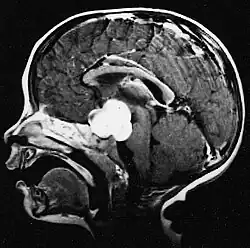

Na ressonância magnética, um tumor intracraniano aparece como uma lesão maciça que pode se tornar mais luminescente após o uso do agente de contraste. No entanto, há sempre uma anomalia de sinal na ressonância magnética, que indica a presença de neoplasia ou edema vasogênico. Normalmente, o aumento da luminescência (realce pelo contraste) é indicativo de um tumor de grau mais alto de malignidade. Um anel contrastante é característico do glioblastoma, com a porção luminescente correspondendo à parte vital do tumor maligno e a área mais escura-hipointense à necrose tecidual.

Glioblastoma

Os tumores de células gliais mais comuns e malignos são os glioblastomas. Consistem em uma massa heterogênea de células de astrocitoma pouco diferenciadas principalmente em adultos. Geralmente ocorrem nos hemisférios cerebrais, mais raramente no tronco cerebral ou na medula espinhal. Exceto em casos muito raros, como todos os tumores cerebrais, eles não se estendem além das estruturas do sistema nervoso central.

O glioblastoma pode surgir de uma forma difusa (II. grau) ou um astrocitoma anaplásico (III. grau) se desenvolvem. Neste último caso, é chamado de secundário. No entanto, quando ocorre sem antecedentes ou evidência de malignidade prévia, é referido como primário. Os glioblastomas são tratados com cirurgia, radioterapia e quimioterapia. Eles são difíceis de curar e há poucos casos que sobrevivem além de três anos.

A ressonância magnética geralmente mostra uma lesão maciça com realce de contraste envolvendo o cerebelo. Como mencionado acima, o meduloblastoma tem alta propensão a infiltrar localmente as leptomeninges, bem como a se espalhar pelo espaço subaracnóideo, envolvendo os ventrículos, a convexidade cerebral e as superfícies leptomeníngeas da coluna. Consequentemente, é necessário trazer todo o eixo cranioespinhal em ressonância.